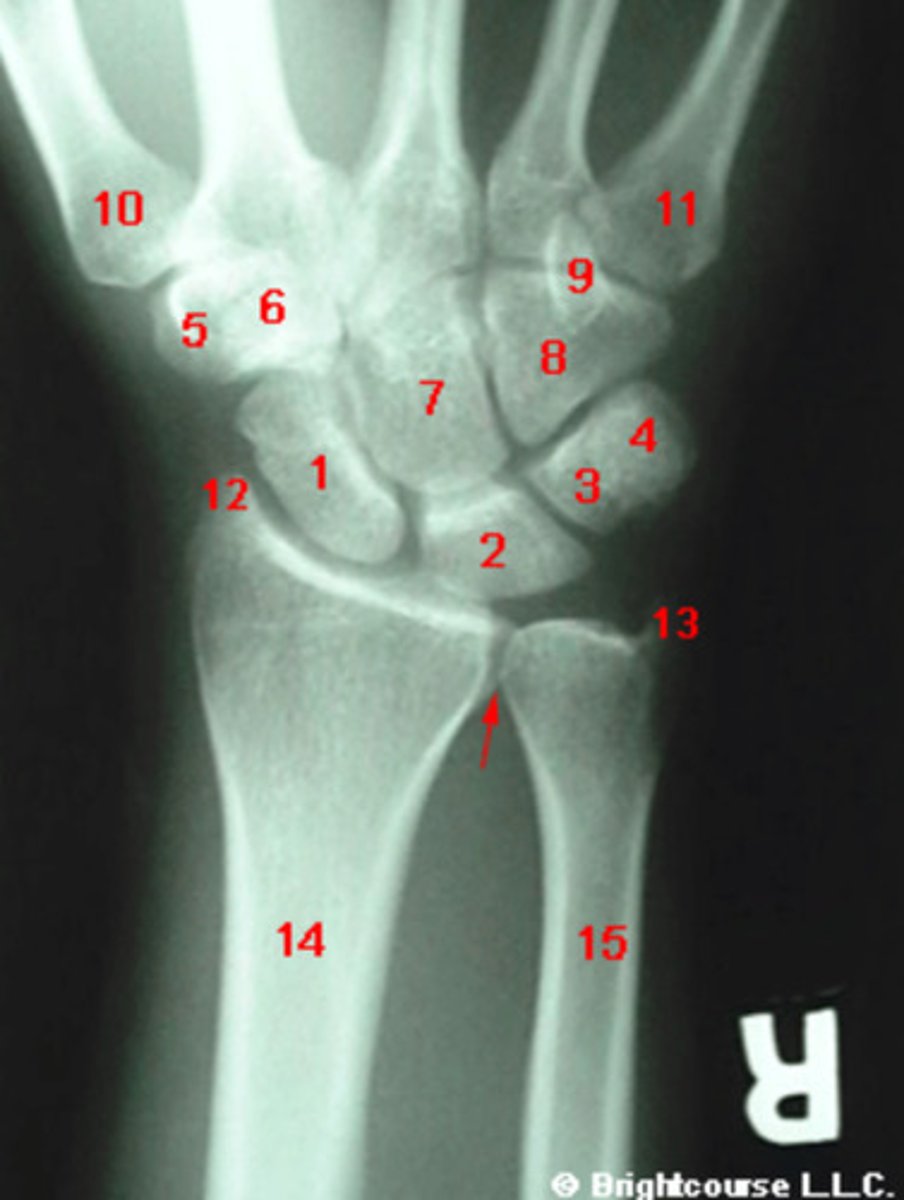

PA, internal oblique, and lateral

What are the standard plain film radiographic projections for the wrist?

What is the normal range for the Carpal angle?

What is the normal range for the radioulnar angle?

What is the normal range for the radius angle?

What conditions can alter the normal carpal alignment?

Negative ulnar variance

An ulnar variance measuring 15mm is considered to be?

Capitate

What structure is indicated by number 7?

Scaphoid

What structure is indicated by number 1?

Lunate

What structure is indicated by number 2?

What is the most commonly fractured carpal bone?

Triquetrum

What structure is indicated by number 3?

Pisiform

What structure is indicated by number 4?

Trapezium

What structure is indicated by number 5?

Trapezoid

What structure is indicated by number 6?

Hamate

What structure is indicated by number 8?

Styloid process of ulna

What structure is indicated by number 13?

Styloid process of radius

What structure is indicated by number 12?

Hook of the hamate

What structure is indicated by number 9?

Base of the first metatarsal

What structure is indicated by number 10?

3 arcs of carpal alignment

What is being assessed in this image?